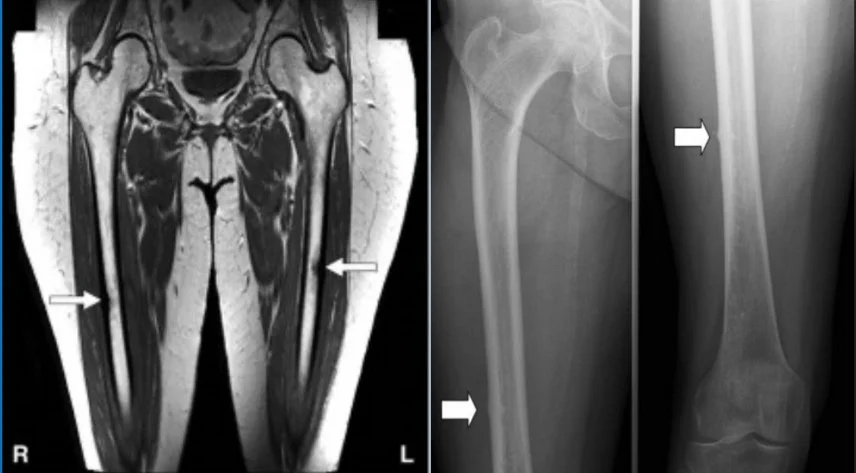

After gathering the above information, the patient was immediately referred to a physician for diagnostic imaging. MRI being the gold standard for diagnosing stress fractures. An MRI confirmed a femoral shaft stress reaction and the patient was also referred for a bone density scan and blood work (vitamin D and Calcium levels specifically).